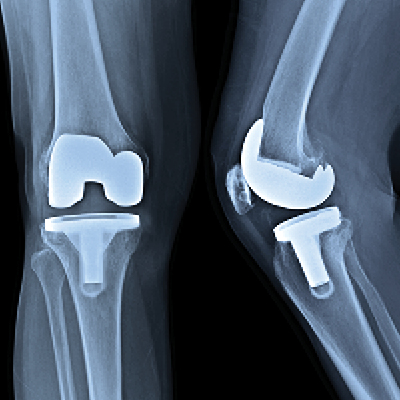

Sometimes arthritis affects the entire knee joint, but often it degrades just one area (the inside or outside of the knee or even just the kneecap). During total knee replacement surgery, the surgeon removes the damaged cartilage and bone from the entire knee joint, then replaces the joint with a metal and plastic prosthesis (implant).

In a partial knee replacement, only one surface of the joint is removed and replaced with a smaller implant. Roughly, about 15% of end-stage knee arthritis patients are good candidates for a partial knee replacement.